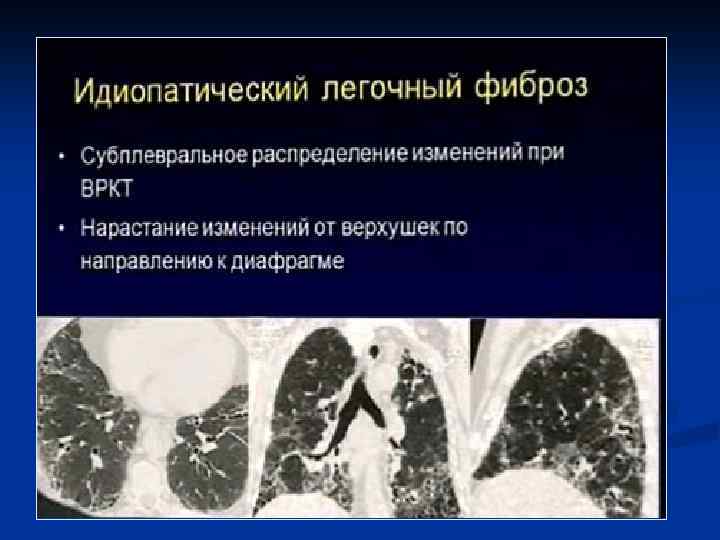

ИТАК, n Долевые и очаговые инфильтративные изменения обычно характерны для бактериальных пневмоний n Сетчатые интерстициальные изменения или сочетание инфильтративных и интерстициальных изменений типичны для пневмоний вирусной, микоплазменной, хламидийной и пневмоцистной природы, а милиарные поражения — для туберкулеза легких, генерализованного сальмонеллеза, грибковых поражений. n Инфильтративные или интерстициальные изменения в сочетании с лимфоаденопатией типичны для туберкулеза легких и пневмоний, вызванных грибами, микоплазмой, хламидиями, вирусами кори и ветряной оспы.